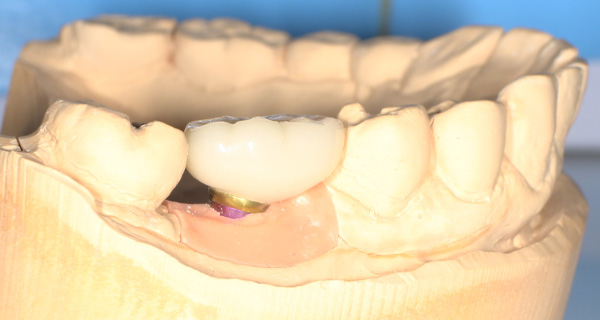

インプラント手術から3ヵ月後、型どりをして、仮歯を製作しました。

レントゲン画像 -

仮歯の調整期間を経て、セラミックの歯が入りました。

レントゲン画像 治療前 インプラント治療後